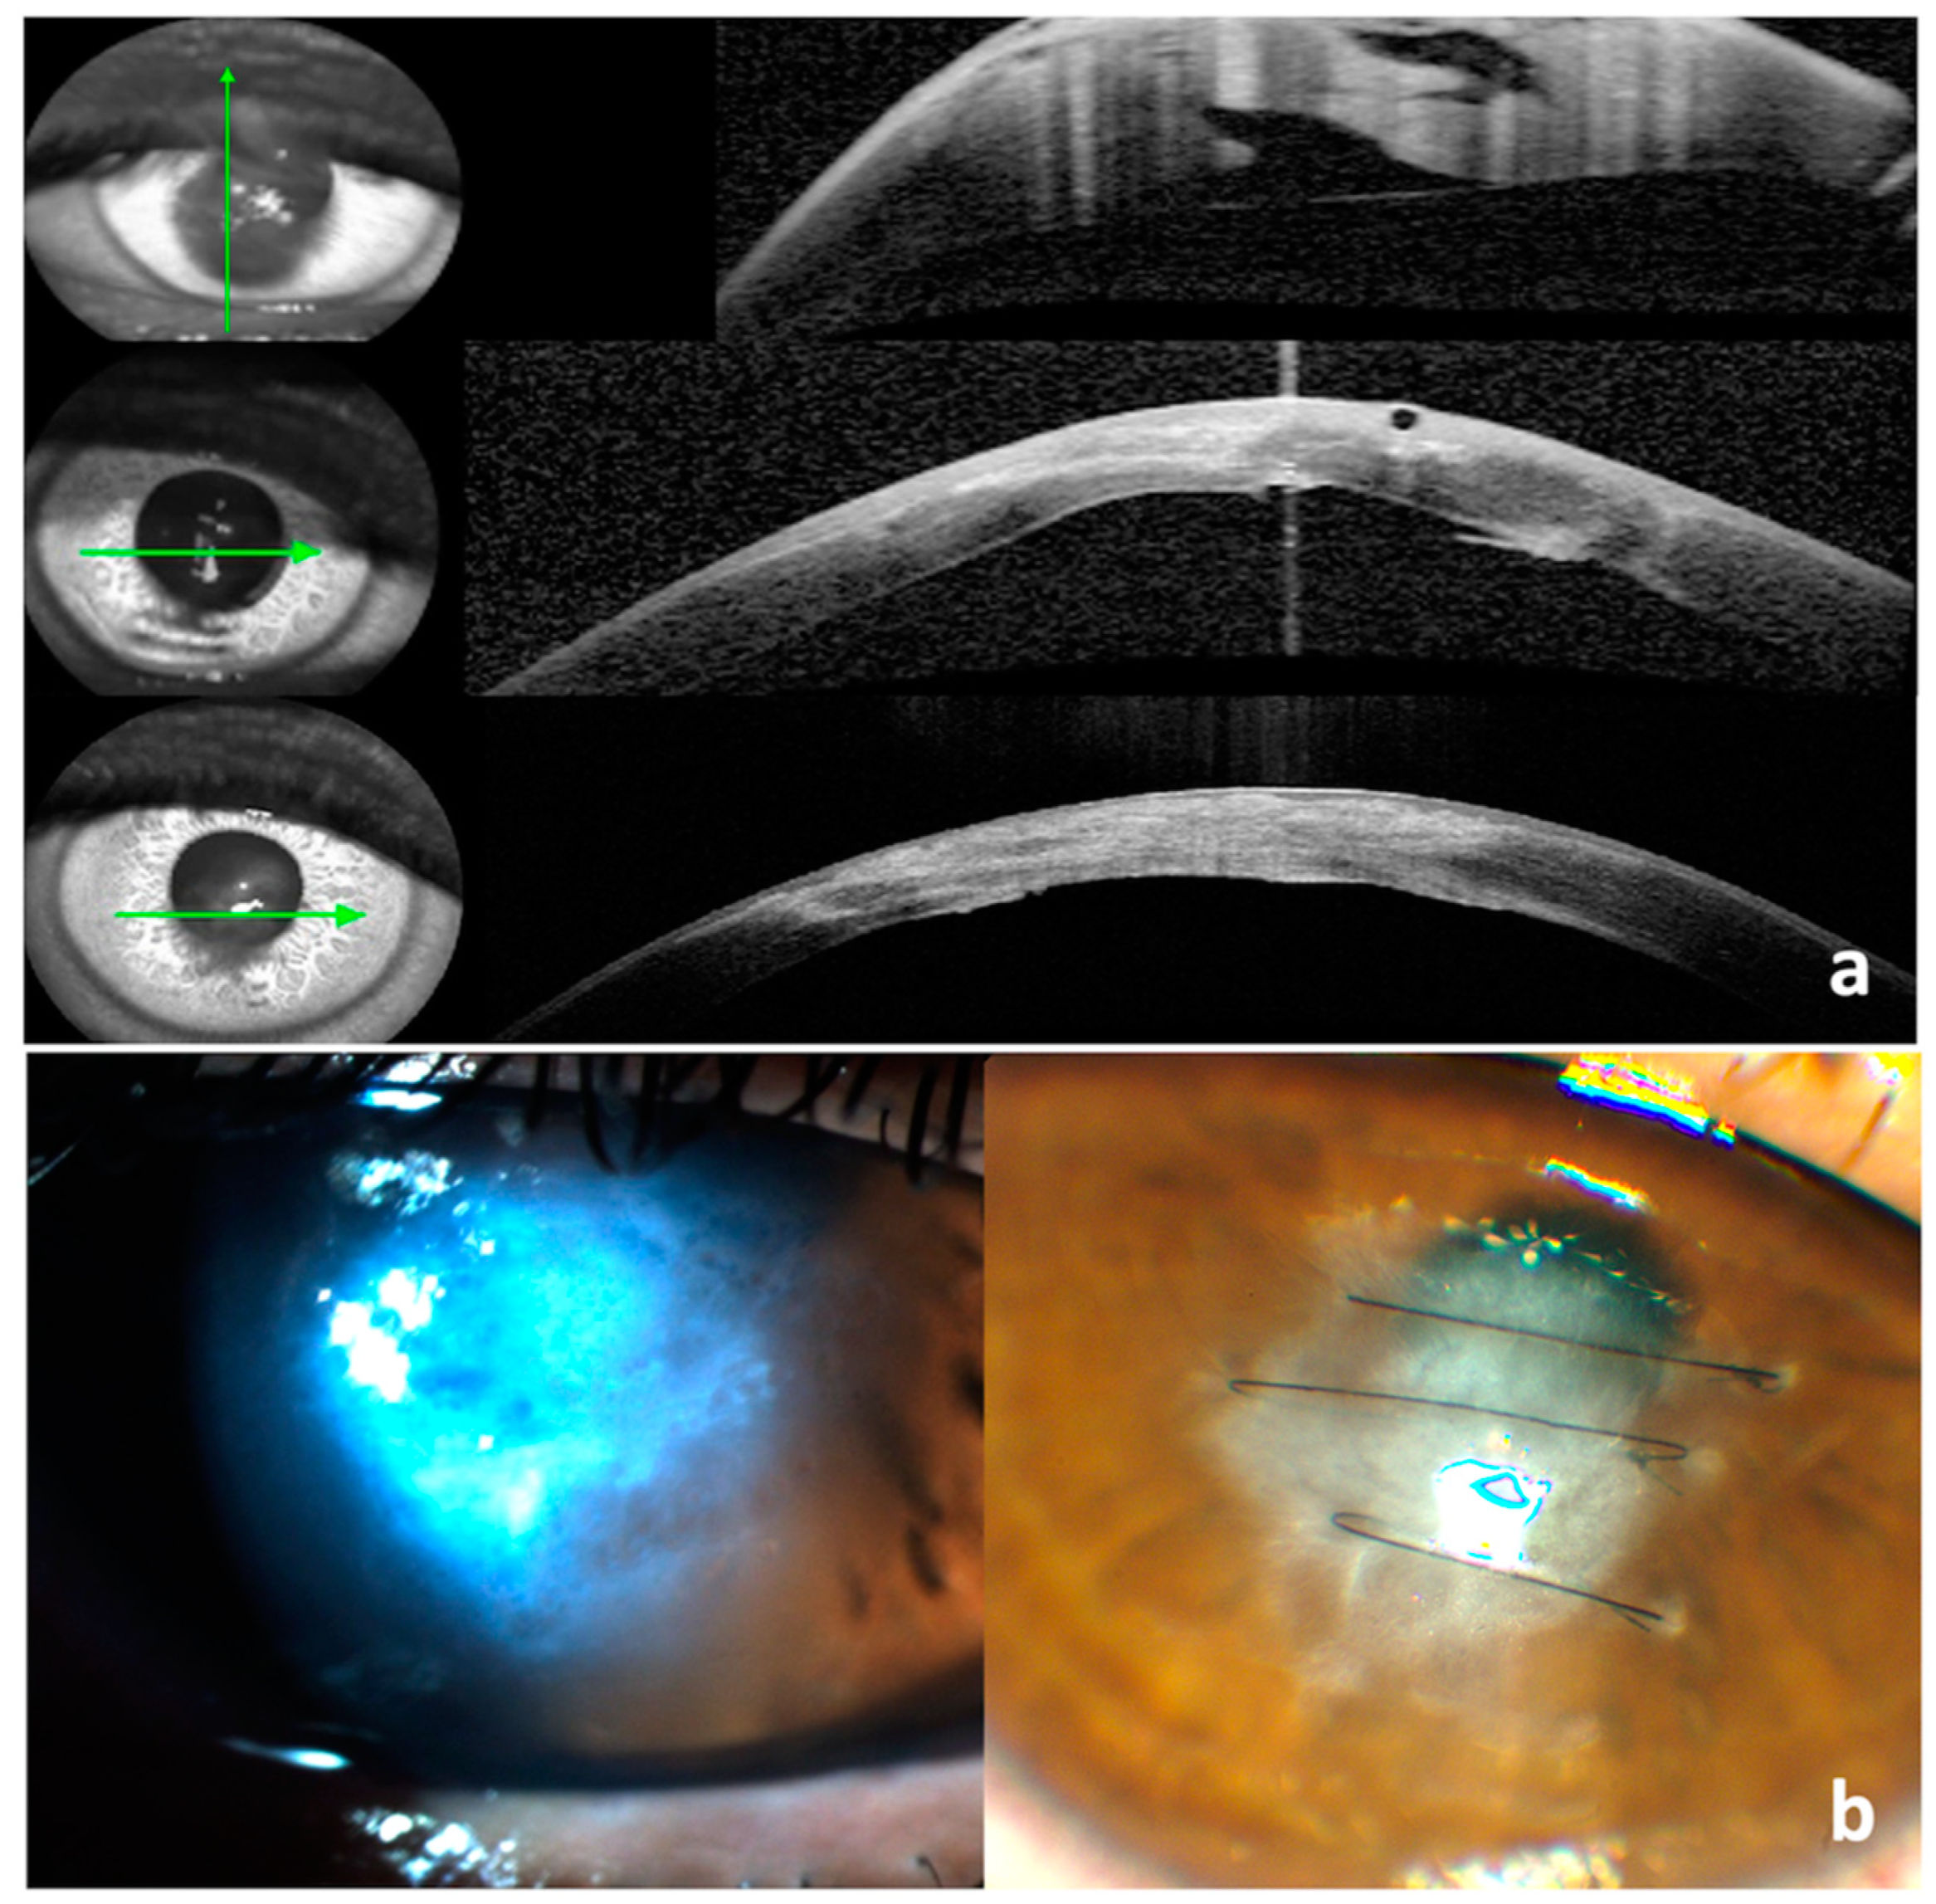

All patients had ASOCT at presentation to locate the Descemet tear. However, this diagnostic tool was not conclusive in a few cases with significant corneal oedema and stromal cleft. After obtaining informed consent, the theatre procedure was performed under local or general anaesthesia, based on the patient’s preference. A small air bubble was injected into the anterior chamber to visualize the Descemet tear, which revealed the break/s and demonstrated their orientation and length within 10 min. This technique was especially beneficial in cases with extensive oedema, where ASOCT failed to locate the Descemet break. This was followed by placing 3 to 6 full-thickness interrupted 10-0 nylon corneal sutures perpendicular to the Descemet break/s (Video S1, Figure 1a–f). Care was taken not to touch the crystalline lens. The sutures were tied tighter than usual, expecting some loosening on the resolution of corneal oedema and the knots were buried in the stroma. The small air bubble was removed at the end of the procedure, and intracameral cefuroxime was injected. The eyes were covered with a clear shield. Patients were prescribed topical Tobramycin and Dexamethasone combination eye drops (Tobradex®, Alcon Laboratories, Fort Worth, Texas, USA) four times a day for two weeks, and a follow-up was arranged in one week.

Figure 1. (a) Injecting the air bubble in the AC via paracentesis, (b,c) the appearance of two Descemet breaks, (d) placing the perpendicular full-thickness suture, (e) making the suture tight, and (f) four full-thickness suture perpendicular to the Descemet breaks.

Figure 2. (a) Anterior segment OCT: pre-op (left) with apex pachymetry of 1096 µ and 10 days post-op (right) with apex pachymetry of 466 µ. The arrow shows the level of the scan. (b) Loose corneal sutures after resolution of corneal oedema.

Figure 3. Anterior segment OCT: pre-op with a stromal cleft (top 2 scans) and apex pachymetry of 1380 µ, and 8 days post-op (bottom 2 scans) with apex pachymetry of 548 µ. The arrow shows the level of the scan.